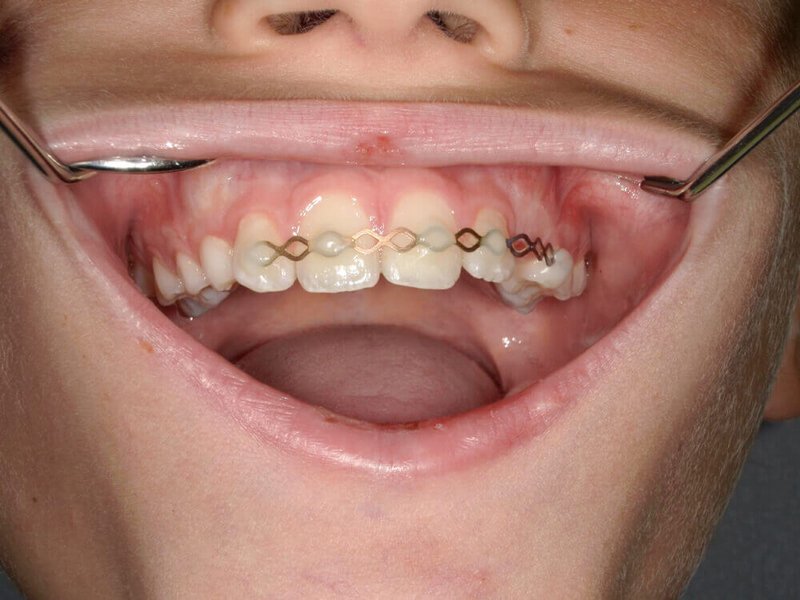

Nach Infiltrationsanästhesie und Desinfektion konnte eine direkte Überkappung der Pulpaöffnung mit MTA Zement erfol-gen. Die Passgenauigkeit des Zahnfragmentes wurde geprüft; die Oberflächen an den jeweiligen Bruchstellen geätzt, gespült und getrocknet. Mit Hilfe von Primer, Bonding und fließfähi-gem Komposit (Flow) konnte das Bruchstück befestigt werden. Anschließend wurde zur Sicherung eine TTS-Schiene (Titanium Trauma Splint) mit Hilfe von Flow angebracht. Die Nachkontrol-len am Folgetag und eine Woche darauf ergaben eine korrekte Schienenposition, dazu Vitalität und Perkussion des verletzten Zahns. Die Schiene wurde nach 14 Tagen entfernt.

Bei einer Kronenfraktur im Frontzahnbereich bietet sich als minimalinvasive Therapie ein Reattachment des mit-gebrachten Fragments an. Dadurch lässt sich eine stärker invasive Versorgung mit einer Krone vermeiden. Es ist sinn-voll, substanzerhaltend und ästhetisch mit Bonding und Flow zu arbeiten. Eine Überkappung der kleinflächigen Pul-paexposition war in diesem Fall möglich, da die Maßnahme innerhalb kurzer Zeit nach Trauma erfolgte. Ohne endodon-tische Behandlung blieb der verletzte Zahn vital und musste lediglich vorübergehend durch eine flexible Titanschiene fixiert werden. Die Prognose für Zahn 21 und das umgebende Parodont ist sehr gut. Neben dem rein therapeutischen Nut-zen kann diese Art der „Sofortreparatur“ mit dem Bruchstück des eigenen Zahns auch psychologisch entlastend wirken.